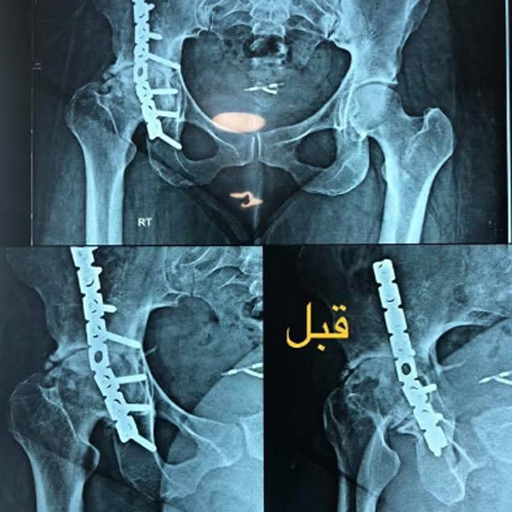

نماذج من حالات دكتور ساهر

يشتهر د. ساهر بمهارته الفائقة في علاج خشونة الركبة، وإجراء عمليات الرباط الصليبي وإصلاح قطع الغضروف الهلالي، إلى جانب تخصصه في تغيير مفصل الركبة والفخذ باستخدام أحدث التقنيات العالمية. بفضل اطلاعه المستمر على التطورات الطبية، يقدم د. ساهر كمال أحدث الحلول الجراحية لتغيير مفصل الفخذ، مع تحقيق نتائج استثنائية تضعه في مقدمة جراحي العظام على المستوى الدولي.